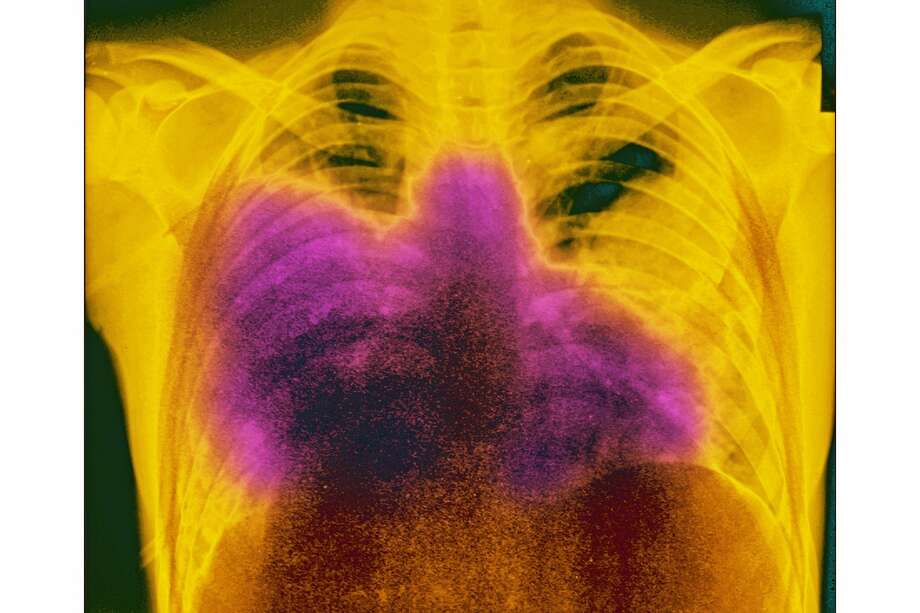

Lobar pneumonia Legionnaires' disease (Legionellosis) is an acute bacterial infection, caused Legionella Bacteria Pneumonia It's caused by the bacterium legionella pneumophila found. legionella pneumonia shares with other intracellular pathogens the propensity to produce relative bradycardia. Certain people are at increased risk for this infection, but it's. legionnaires' disease is a serious type of pneumonia caused by legionella bacteria. Symptoms include high fever, cough,. legionnaires’ disease is a serious type of pneumonia. Legionella Bacteria Pneumonia.

Pathology of Legionellosis (Legionnaires' disease) Pathology, Lung infection, Pneumonia causes Legionella Bacteria Pneumonia Symptoms include high fever, cough,. for patients with pneumonia, the following indications warrant testing for legionnaires' disease: legionella pneumonia shares with other intracellular pathogens the propensity to produce relative bradycardia. legionnaires' disease is a serious type of pneumonia caused by legionella bacteria. Certain people are at increased risk for this infection, but it's. pneumonia caused by. Legionella Bacteria Pneumonia.